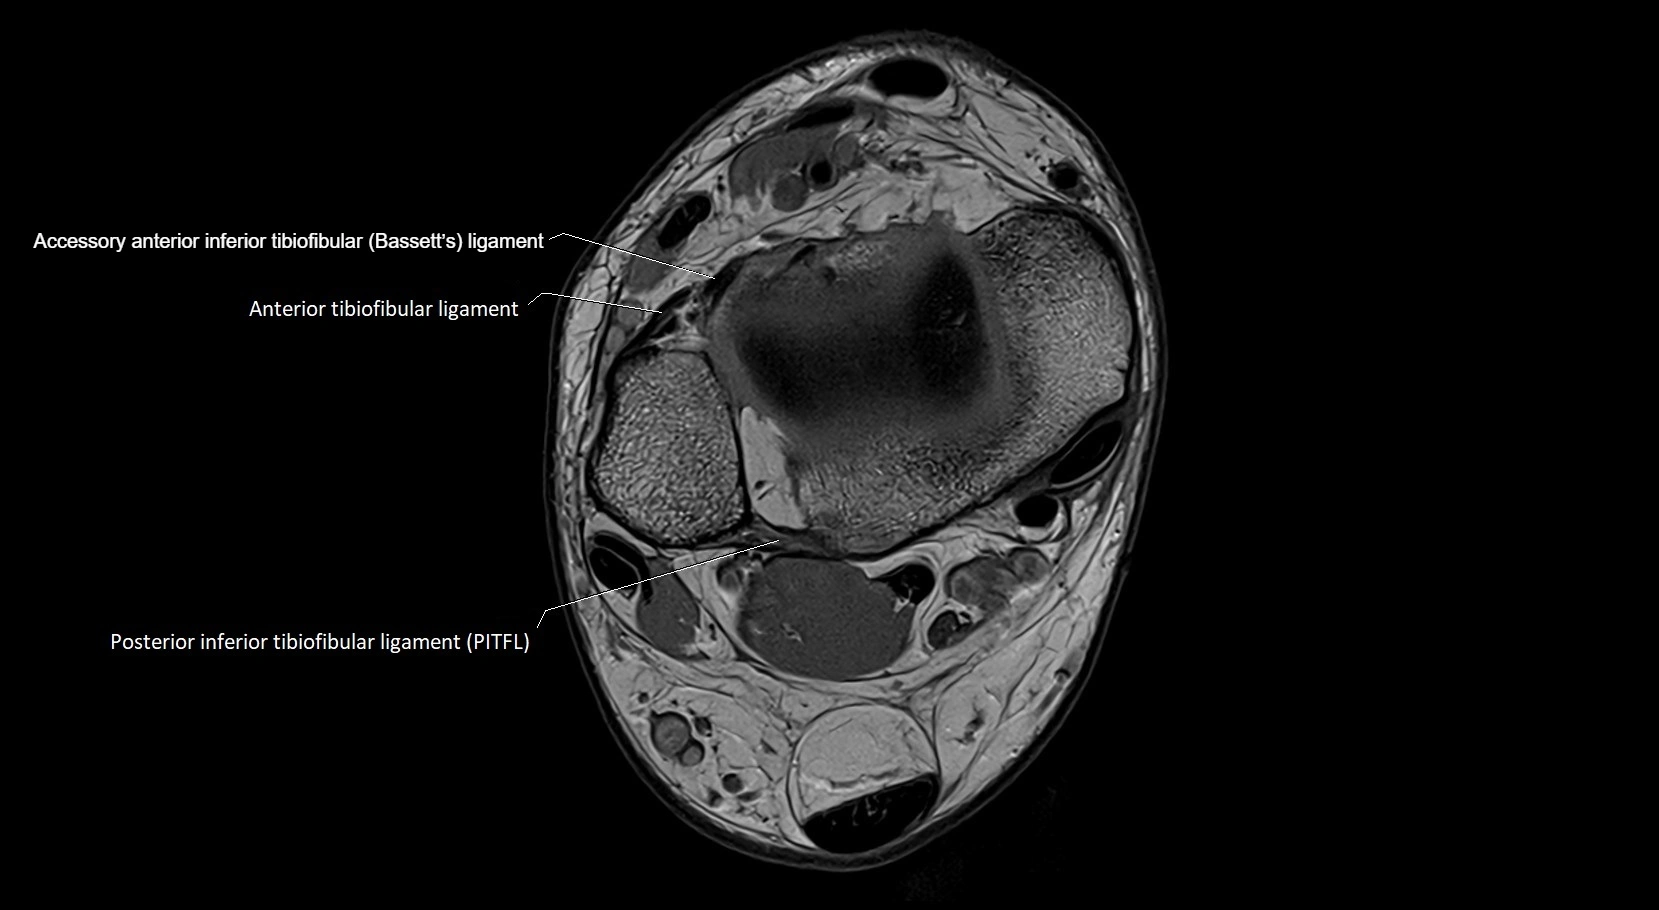

MRI image

image